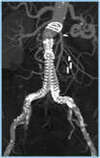

Endoprothèse aortique pour Anévrisme de l'aorte

Depuis 1990, les techniques endo-vasculaires (technique permettant de traiter l’anévrisme sans ouvrir l’abdomen) ont pris le dessus et aujourd’hui il y a plus d’endoprothèse aortique de posées que de chirurgie conventionnelle ne sont réalisées.

Afin de faciliter la mise en place de l’endoprothèse aortique, a été développée depuis plusieurs années de multiples ingéniosités.

Afin de faciliter la pose de celle-ci et en particulier de réaliser le raccordement des deux jambages droit et gauche a été développé un guide aimanté permettant de travailler à l’intérieur de l’anévrisme.

Ces deux guides aimantés l’un vers l’autre vont permettre de se réunir à l’intérieur de la poche anévrismale facilitant ce moment souvent délicat et long.

Cette amélioration technique permet de réduire de façon significative le temps d’exposition du patient au rayonnement ionisant de la radiologie mais aussi de réduire la quantité de produit opaque utilisé qui est néfaste pour les reins.